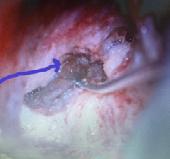

locii sau transmastoidian. În ultimul timp a mai fost descrisă o tehnică chirurgicală care implică obliterarea ferestrei rotunde cu scopul eliminării uneia dintre ferestre. Materialele folosite pentru obliterare sunt fascie, cartilaj, pulbere de os, ciment biologic sau hidroxiapatită (3). În literatură există multe controverse în ceea ce privește cea mai bună tehnică chirurgicală. Avantajele abordului transcranian sunt că se poate identifica și acoperi defectul osos la vedere, iar unii autori raportează rezultate foarte bune folosind atât obliterarea cât și acoperirea defectului (8). Dezavantajele acestei metode sunt pericolul de fistulă LCR, și complicațiile legate de chirurgia cerebrală, motiv pentru care s-a descris tehnica prin abordul endoscopic a bazei craniului. Abordul transmastoidian clasic sau endoscopic cu irigare abundentă, este mai puțin riscant iar mai mulți autori raportează ameliorarea simptomelor în 80% dintre pacienți. Obliterarea canalului pare mai sigură ca durabilitate deoarece în acoperirea defectului simptomele pot reapare, se pare că prin resorbția în timp a materialului folosit. La ora actuală se speră în folosirea unor proteze personalizate 3D sau adezivi biologici care pot fi puse astfel încât să fie prezervată funcția CSS. Pacienții pentru chirurgia de revizie trebuie atent selectați (9) Fig 3. Imagini inraoperatorii a. CSS - linia albastră, b. Obliterarea CSS cu fascie de muşchi temporal.

Fig. 3b Fig. 3a